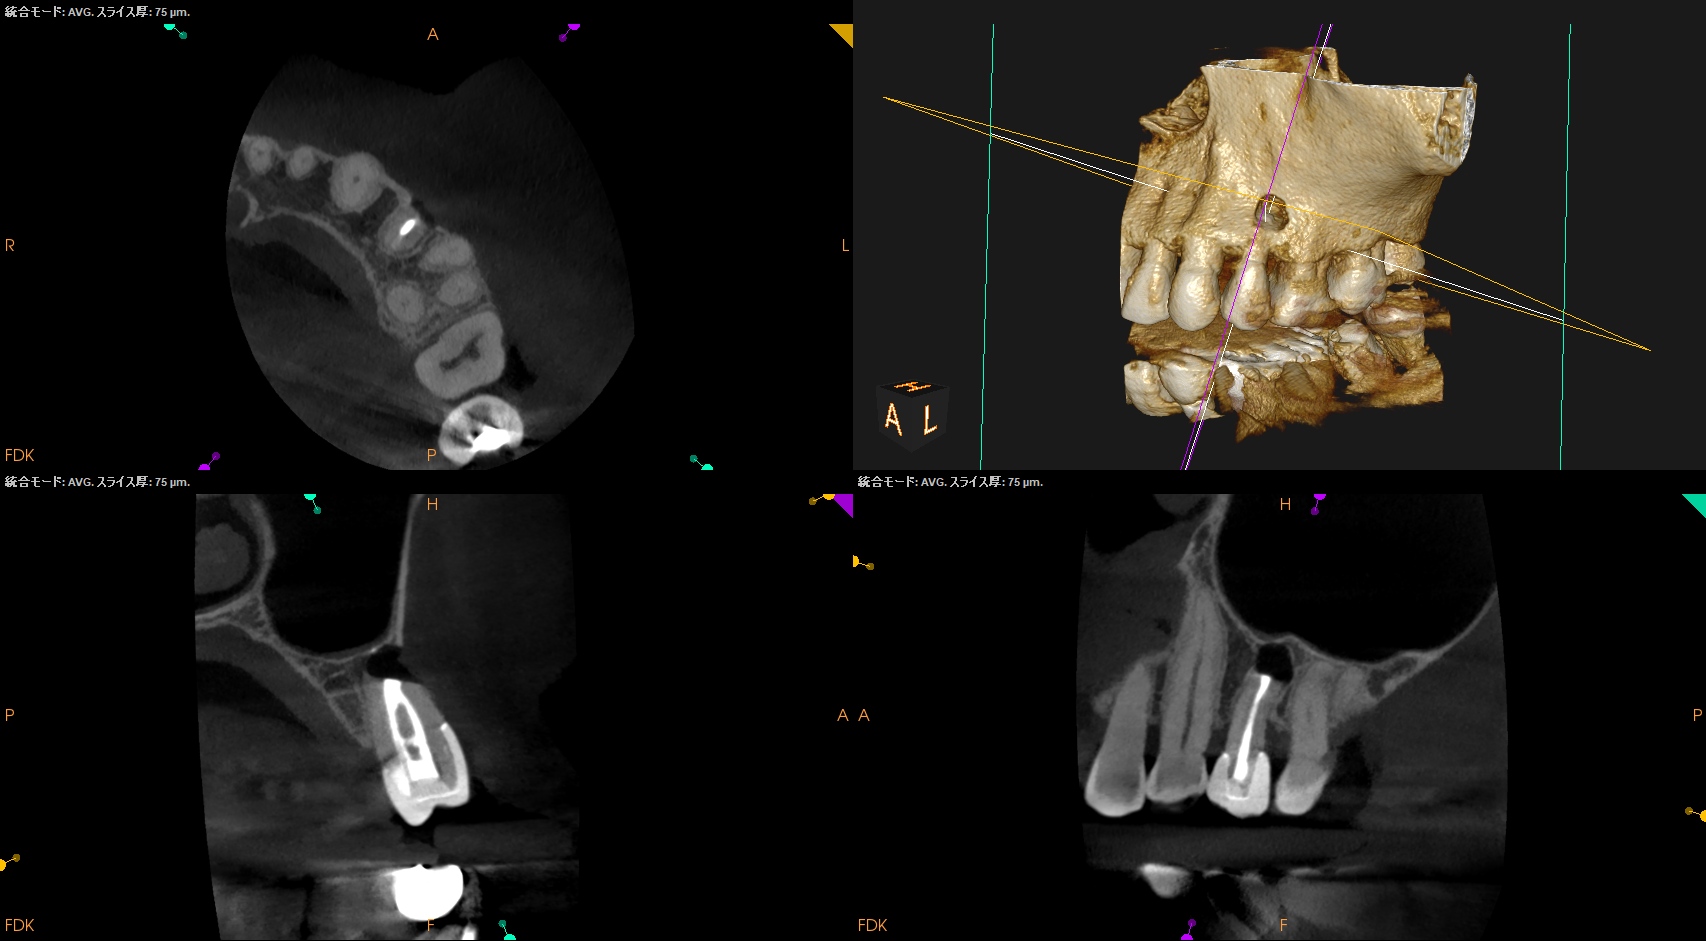

CBCT(2025.8.22)

#13 遠心のマージンが歯肉縁下でクラウンが不適合だ。ここにものが詰まるようだ。

これが患者さんの主訴である。

また、根尖病変があり根管形成・根管充填が太くなされていることからApicoectomyへ移行することになった。

#13 Apicoectomy(2025.10.7)

術後にPA, CBCTを撮影した。

問題はないだろう。